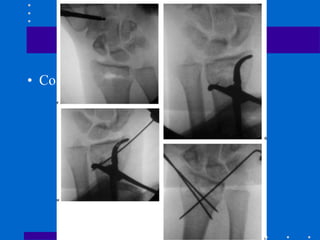

Pinagem e gesso

• 1º estilóide 2º coluna intemediária (fossa

lunar) de dorsal ulnar para proximal radial

3º fragmentos impactados podem ser

suportados por fios subcondrais transversais

Kapandji

• Fios intrafocais radial e dorsal servindo de

suporte

• Original 1 fio dorsal e 1 estilóide

• Modificada: 2 fios dorsais e 1 estilóide

• Tendência a translação do fragmento distal

• Efetivo para fraturas extra-articulares